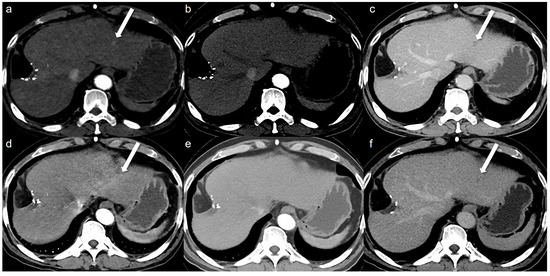

| SDCT | LCLM CT | p-Value | Inter-Reader Agreement (Gwet’s AC2) | |

|---|---|---|---|---|

| Overall image quality | 4.94 ± 0.24 [4.10, 5.78] | 4.82 ± 0.46 [4.00, 5.64] | 0.001 | 0.929 [0.893, 0.965] |

| Hepatic artery clarity | 4.83 ± 0.50 [4.01, 5.64] | 4.93 ± 0.32 [4.09, 5.76] | 0.047 | 0.961 [0.932, 0.985] |

| Contrast of the liver | 4.90 ± 0.31 [4.07, 5.72] | 4.97 ± 0.24 [4.13, 5.81] | 0.032 | 0.959 [0.932, 0.985] |

| Image noise | 4.93 ± 0.25 [4.10, 5.77] | 4.83 ± 0.42 [4.01, 5.65] | 0.002 | 0.893 [0.848, 0.937] |